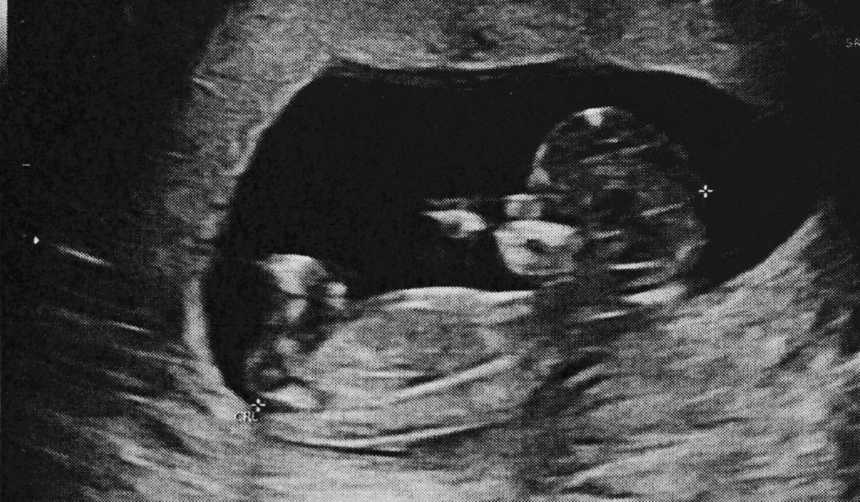

O sarcină ectopică apare atunci când embrionul se dezvoltă în afara uterului, cel mai frecvent în trompele uterine, dar uneori și în ovare, cervix sau pe cicatricea unei cezariene anterioare. Aceste sarcini reprezintă aproximativ 1% din totalul sarcinilor, iar șansele ca o sarcină să se dezvolte complet în afara uterului sunt de aproximativ 1 la 11.000. În majoritatea cazurilor, când sarcina ectopică eșuează, țesutul embrionar este reabsorbit natural de corpul mamei, mai ales dacă sarcina nu a depășit 12 săptămâni. După această perioadă, scheletul fătului conține os, iar organismul nu îl poate reabsorbi. Sistemul imunitar al mamei recunoaște fătul mort ca pe un corp străin și îl acoperă cu calciu, un proces asemănător mumificării, pentru a proteja organismul de infecții. Această masă calcificată poate rămâne în abdomen luni sau chiar decenii, până când este descoperită sau îndepărtată chirurgical.

Doar între 1,5 și 1,8% dintre sarcinile ectopice nerezolvate ajung să se transforme în lithopedion, ceea ce explică raritatea fenomenului. Cazurile documentate în literatura medicală mondială sunt extrem de puține, însă există dovezi istorice ale acestui fenomen, inclusiv un lithopedion descoperit într-o săpătură arheologică la Bering Sinkhole, Texas, datând din 1100 î.Hr.